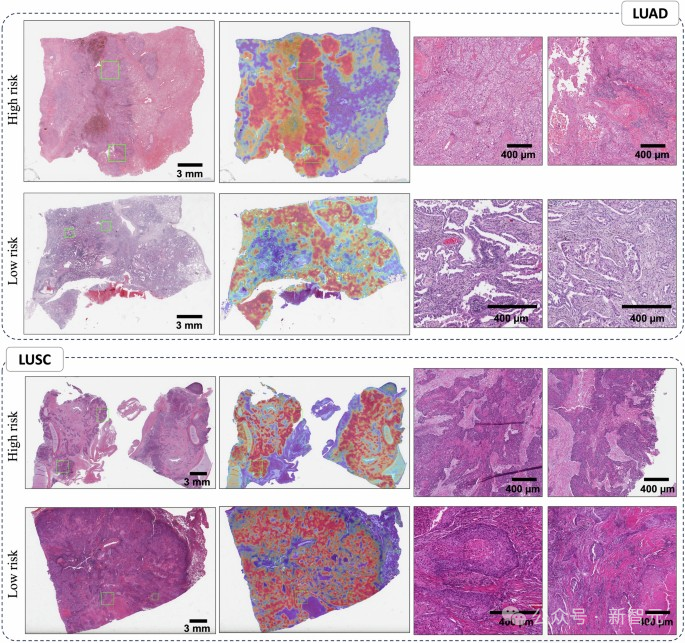

该模型在图像上识别出与肿瘤侵袭性和患者生存率相关的明显模式。

为了可视化特定的区域,CHIEF在图像上生成了热图。当人类病理学家分析这些由AI生成的热点时,他们发现了一些反映癌细胞与周围组织相互作用的有趣信号。

模型注意力的可视化显示了肺癌患者生存预测中的重要区域

其中一个特征是,在长期生存者的肿瘤区域中,免疫细胞的数量比短期生存者更多。Yu指出,这一发现有其合理性,因为更多的免疫细胞可能表明免疫系统已被激活来攻击肿瘤。

在观察短期生存者的肿瘤时,CHIEF识别出了一些需要关注的区域。这些区域的特征包括各种细胞成分的异常大小比例、细胞核上更多的非典型特征、细胞之间较弱的连接,以及肿瘤周围区域中较少的结缔组织。

这些肿瘤周围还有更多的死亡细胞。例如,在乳腺肿瘤中,CHIEF指出组织内的坏死(或细胞死亡)是一个需要关注的区域。另一方面,生存率较高的乳腺癌患者肿瘤周围,更有可能保持类似于健康组织的细胞结构。

研究团队指出,与生存率相关的视觉特征和需要关注的区域因癌症类型而异。